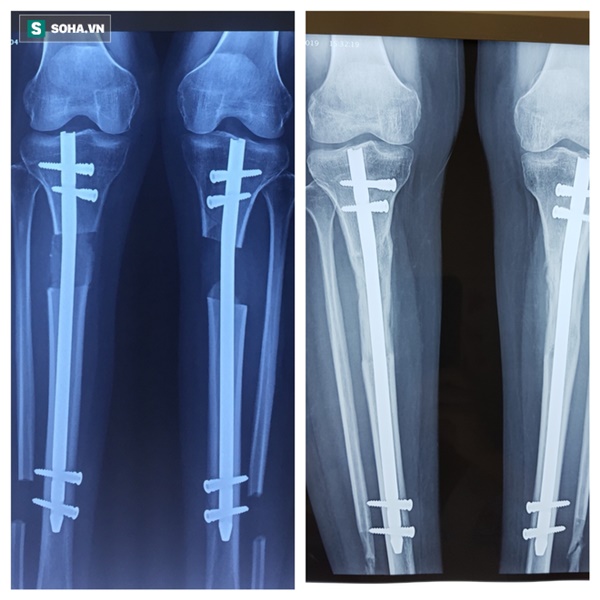

Phim chụp xương của Hưng được kéo ra và 1 năm sau can xương đã bắt đầu đầy.